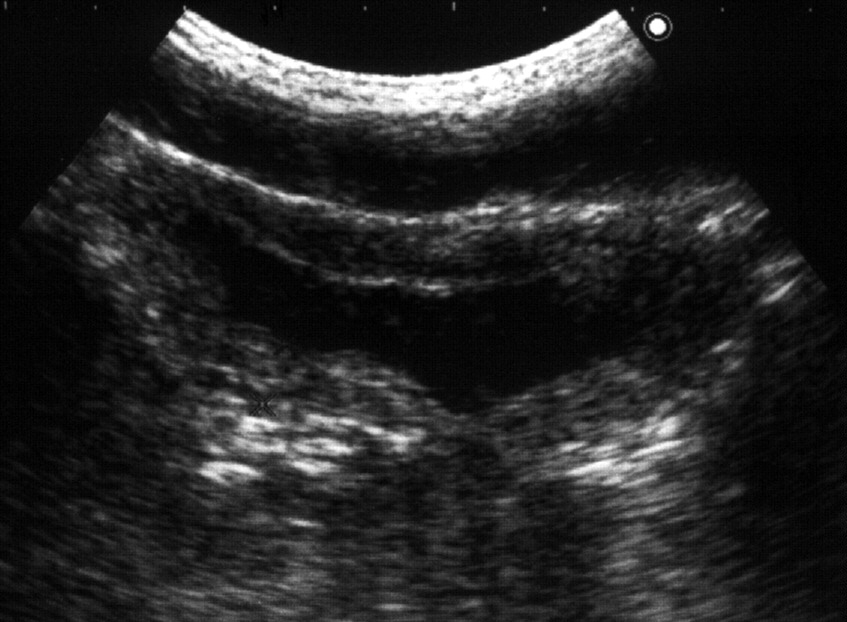

Рис. 6. В дальнейшем появляется трабекулярность его стенок: 1 − мочевой пузырь; 2 − простата; 3 − стенка пузыря утолщена, с выраженной трабекулярностью. (Продольное сканирование, конвексный датчик 5 МГц, “Logiq-500”).

Наиболее часто гипертрофия стенок связана с нарушением оттока мочи вследствие инфравезикальной обструкции. Ее причинами могут быть доброкачественная гиперплазия или рак предстательной железы, функциональный или органический стеноз шейки мочевого пузыря (болезнь Мариона), стриктура уретры. При прогрессировании заболевания и увеличении объема остаточной мочи утолщение мышечных пучков становится неравномерным, внутренняя поверхность мочевого пузыря принимает трабекулярный вид (рис. 6). Длительное существование хронической задержки мочи приводит к дальнейшему истончению стенок пузыря (рис. 7). Объем остаточной мочи может при этом достигать 1 л и более.